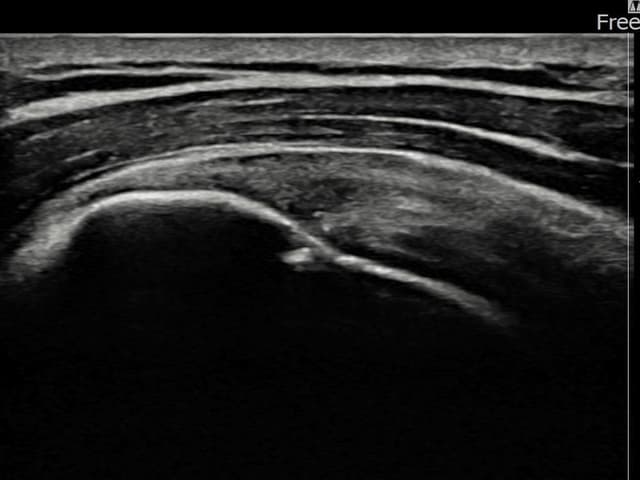

[経過期間: 23.07.31~23.09.27]

[縫縮術] 超音波検査にて左 棘上筋腱 부착부 광범위 部分断裂(13mm × 5mm (腱厚の約65%欠損))を確認。縫縮術施行後、腱の連続性が回復し、日常生活に復帰されました。